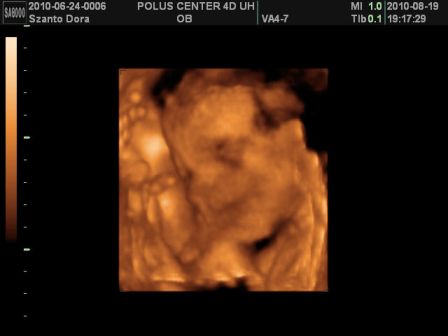

Basszus! Hívtam a kórházat, kiderült a dokim szabin, csak jövő héten szerdán lesz, de menjek be mindenképpen az ügyeleteshez! Na, anyuval felkerekedtünk és irány a kórház. Először csináltak egy uh-t! Dani épp fent volt és akkorákat rúgdalt, h patogott a nőci kezében a vizsgáló kütyü!

Megint nagyobbra mérték egy héttel, szóval továbbra is tartjuk a november elejét, mint születés. És farfekvéses a drágám egyelőre...

Viszont, most már 1360g volt a súlya az 1 héttel ezelőtti 1160g-hoz képest!